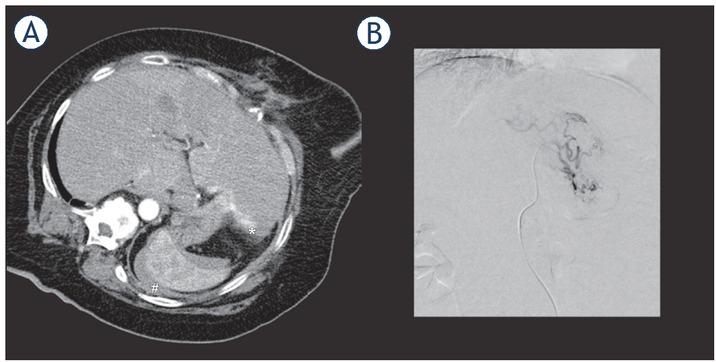

Figure 1